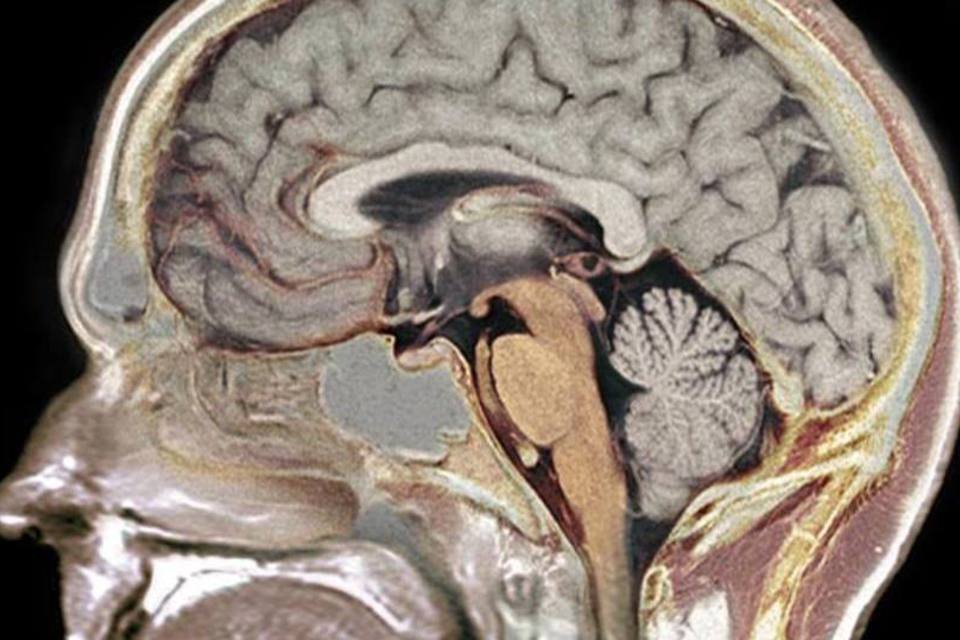

Cérebro humano (Garpenholm/Wikimedia Commons)

São Paulo — Por mais que tenhamos a ajuda de smartphones, tablets e celulares, nenhum hardware é mais valioso para a rotina do que o cérebro.